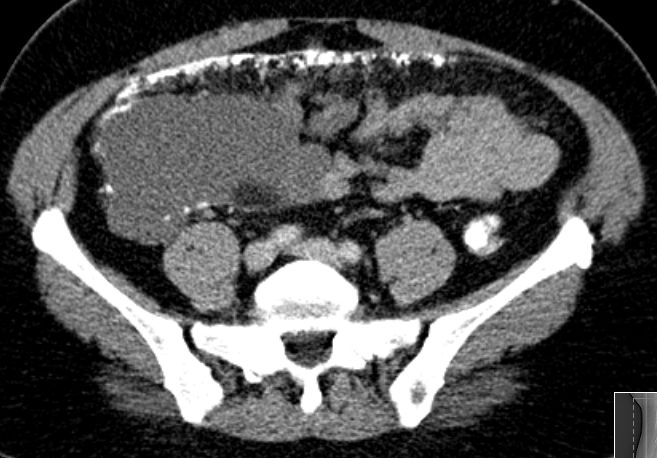

| primäre Tumoren | primäres Peritonealkarzinom | biologisch mit Ovarial- und Tubenkarzinom verwandt. | 51-jährige Frau mit primärem Peritonealkarzinom.![]() |